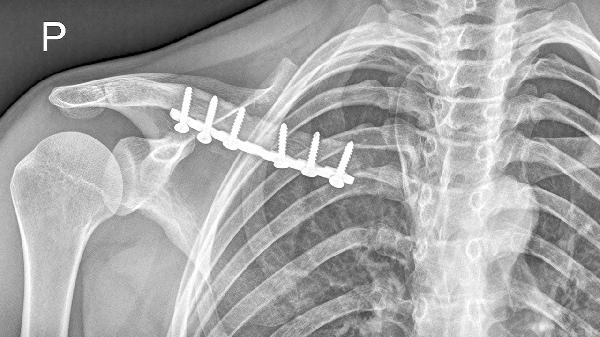

2、外伤史

右侧锁骨骨折愈合后可能出现骨痂过度增生或畸形愈合。既往外伤史是重要线索,可能伴随局部压痛或活动受限。需通过X线检查评估愈合情况,严重畸形需考虑矫形手术。